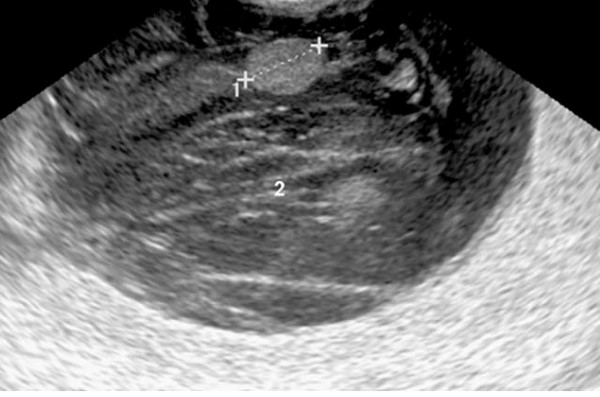

Метастазы колоректального рака

Типичными признаками метастазов колоректального рака были: округлая форма каудальной части опухоли, наличие папиллярных разрастаний и наличие некроза твердой части. Опухоли были преимущественно с гиперэхогенными перегородками в основном с гипоэхогенной или гетерогенной твердой частью. Имеющиеся папиллярные разрастания от изоэхогенных до гиперэхогенных, растущих из тонких перегородок и являющихся специфическими для метастазов колоректального рака, наблюдались у 5/32 (15,6%) опухолей (рис.2).

Рис.2. Метастазы колоректального рака: многокамерная-солидная опухоль с типичной округлой формой (2) с папиллярными разрастаниями из перегородок (1).